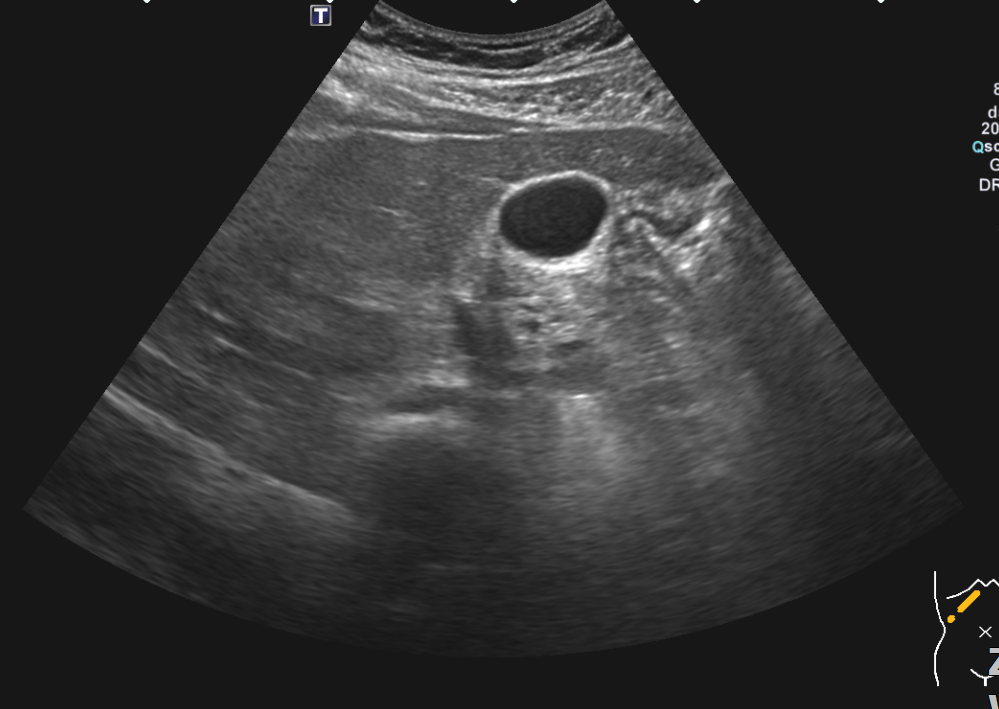

복부초음파 신장 물혹 보이나요? 사진올려봐요

신장물혹 0.6cm mri에는 나오는데 복부초음파에는 소견이없어서요

• 4번 째 사진

올려주신 사진 중 우측 신장이 찍힌 영상은 한 장이며 단면 영상만으로는 물혹 유무를 확인할 수 없습니다.